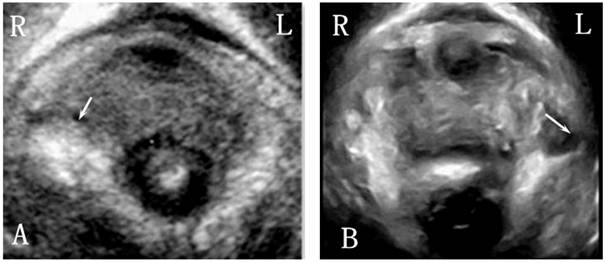

3D ultrasound performance of pelvic floor in the POP group

The levator hiatus increased in size and had an oval or round shape. In 36 (72%) patients, the levator hiatus axis departed from the pelvic floor axis (Fig. 3B). The puborectalis in 18 (36%) cases developed avulsion (Fig. 4), 10 had the unilateral right-sided avulsion (4 cases full avulsion, 6 partial avulsion), 6 had unilateral left-sided avulsion (2 cases full avulsion, 4 partial avulsion) and 2 had bilateral full avulsion. In the levator hiatus at rest, 23 (46%) cases display abnormal organ arrangement. While on maximum Valsalva, 48(96%) cases displayed abnormal organ arrangement, including 18 cases cystocele, 8 uterine prolapse, 15 vaginal vault prolapse and 7 rectocele.

Figure 4

Right-sided and left-sided puborectalis avulsed in POP women.

Direct disruption of the pelvic floor muscles or damage to the pudendal nerves and its branches causing denervation of the muscles may lead to a compromised muscle function[25], which was in accordance with the morphological alternations in the puborectalis detected by 3D ultrasound. Dietz et al revealed that women with levator avulsion defects were more likely to develop pelvic prolapse [26]. In this study, the puborectalis avulsion was detected in 18 (36%) cases, which was unilateral or bilateral in the POP patients. However, in the Nullipara group, abnormality in morphology was not found in puborectalis, which was consistent with previous studies [7,27]. These findings indicate that the abnormal morphology of the puborectalis is closely related to the development of POP.